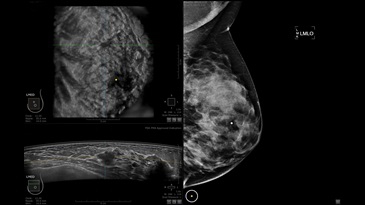

GE INVENIA ABUS – это современный УЗИ аппарат, который создан для точной и эффективной диагностики сканирования с высокой плотностью молочных желез. Выявляемость патологий раковых и предраковых стадий заболевания составляет 55%, что в конечном счете позволяет ставить врачу точные и своевременные диагнозы. Традиционные методы использования маммографии не показывают такой выявляемости, ограничиваясь лишь 3-38%.

УЗИ-аппарат GE INVENIA ABUS позволяет проводить максимально операторонезависимые процедуры, что значительно снижает риск неправильной постановки диагноза и сопутствующие издержки на обработку информации. Система готовит отчет в течение 3-х минут после сканирования, это безусловное преимущество по сравнению с обычным УЗИ сканером.

• датчик с изогнутой апертурой для качественного исследования

• сканирование одной грудной железы в трех проекциях не более 60 сек.;

• обработка результатов за три минуты.

Данное устройство классифицируется, как стационарное, используемое в многопрофильных клиниках, женских консультациях, медицинских центрах. Вес без учета дополнительного оборудования составляет 105 кг. Удобная колесная база позволяет оперативно маневрировать в ограниченных пространствах, в том числе передвигать устройство в коридорах клиники. Большой 17-ти дюймовый монитор с широкими углами обзора выводит максимально качественную картинку в формате Full HD.